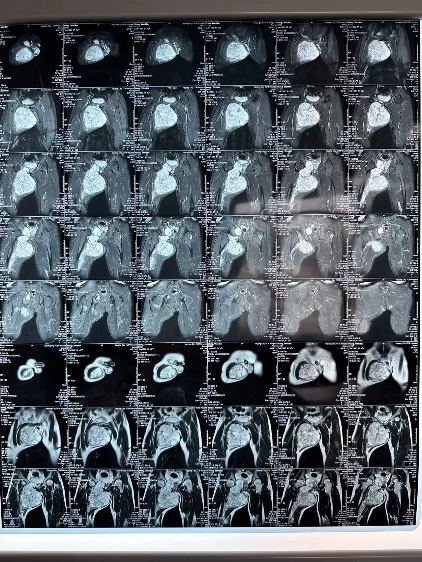

3D建模精准评估 MDT诊疗保驾护航

通过3D建模的精准评估,小王右耻骨软骨肉瘤体积达到了1600立方厘米(1600623.71立方毫米),肿瘤下极自右大腿中段向上,内侧贴大腿皮肤,外侧推压内收肌群及股动静脉,穿过骨盆右闭孔,紧贴右髋臼内侧壁生长,骨盆内占位部分推压膀胱。

图片 7.png

软件测算肿物体积

图片 8.png图片 10.png图片 9.png

3d建模